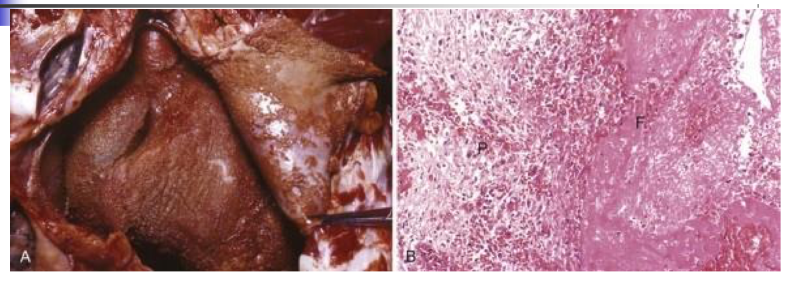

describe what is seen in the image

left = bread and butter pericarditis

describe the 4 types of inflammation (based on exudate)

• serous: mild injury, albumin in exudate, blister, ascites, etc.

• fibrinous: more serious leakage (fibrin), serosal surface